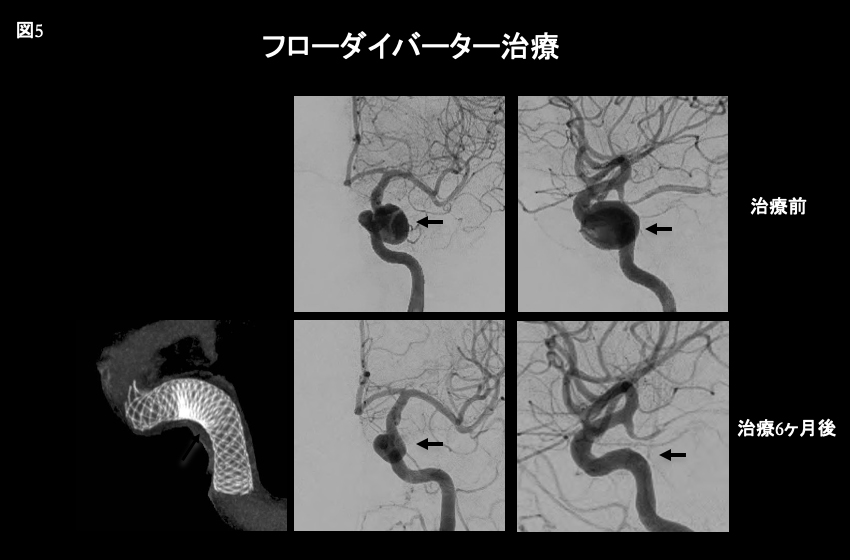

脳動脈瘤治療の大きな変革として、2015年に我が国で初めてFlow Diverter(以下「FD」)が導入され、それまで行われていた外科治療及び血管内治療では根治が困難な脳動脈瘤に対しFDを用いる血管内治療が本邦でも導入された。現在世界中でその臨床実績と研究が進行している(図5)。